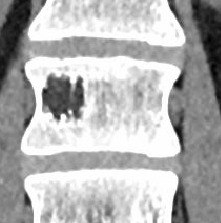

Грыжа межпозвоночного диска Th8-Th9 размером 3-4 мм, протрузии Th2-Th8. Кифоз грудного отдела.

S-образный сколиоз с искривлением около 13 градусов.